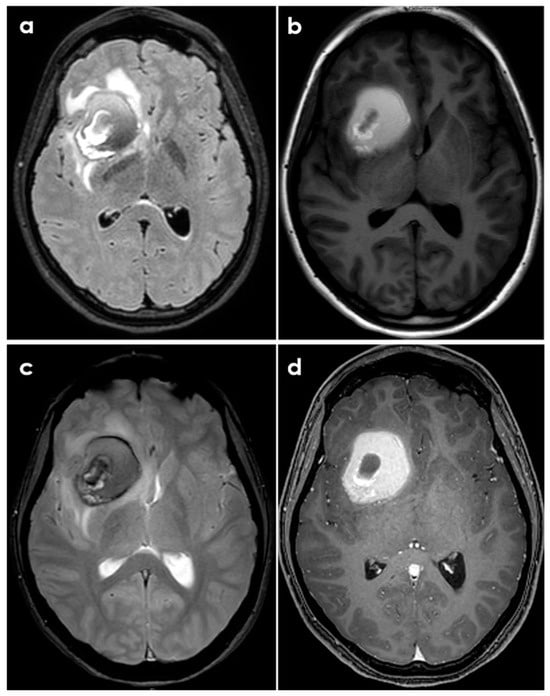

- Case A had a small right frontal cortical hemorrhage with subarachnoid extension and leptomeningeal enhancement over the right hemisphere on post-gadolinium T1-weighted sequences, persisting over the following 3 months together with accumulation of small acute infarcts and persistent leptomeningeal enhancement; CTA was normal, and the diagnosis was achieved by brain biopsy.

- Case B had a right cerebellar hemorrhage on anticoagulant therapy and underwent emergent posterior fossa decompression. In the early follow-up, a new left cerebellar hemorrhage and an acute left pontine infarction occurred; the diagnosis was provided by histopathologic examination of the surgically evacuated tissue.

- Case C had a right parietal lobar hemorrhage with subarachnoid extension, multiple small disseminated acute and subacute infarcts and small rounded sulcal hyperintensities on a fluid-attenuated inversion recovery sequence (dot sign); the diagnosis was provided by the angiographic pattern involving distal branch arteries.

- Case D had a right temporal lobe hemorrhage with small disseminated acute infarcts and chronic microbleeds; diagnosis was provided by angiography, and biopsy was negative.